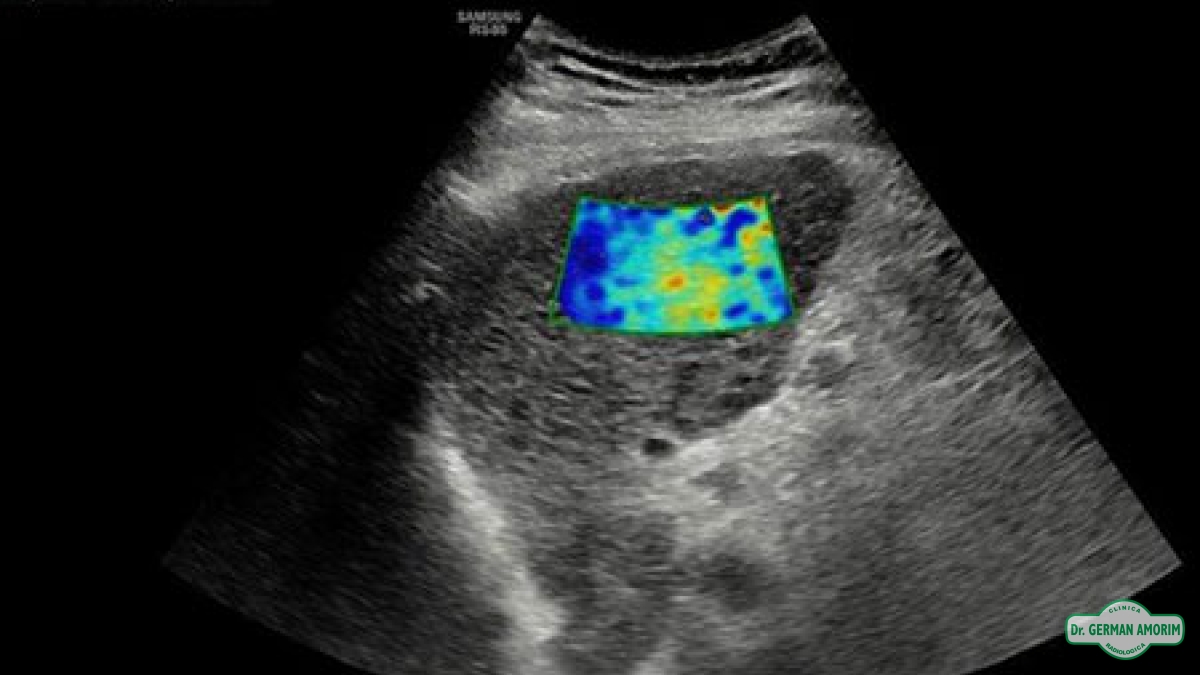

La elastografía es un método de diagnóstico complementario que utiliza los ultrasonidos para valorar la elasticidad o dureza de un segmento de un órgano o de un nódulo en estudio, mediante la tensión y compresibilidad que producen las ondas ultrasónicas en los tejidos del organismo en tiempo real.

Desde su invención, se han descrito múltiples aplicaciones en el estudio de los tejidos de la mama, próstata, tiroides y vasos sanguíneos.